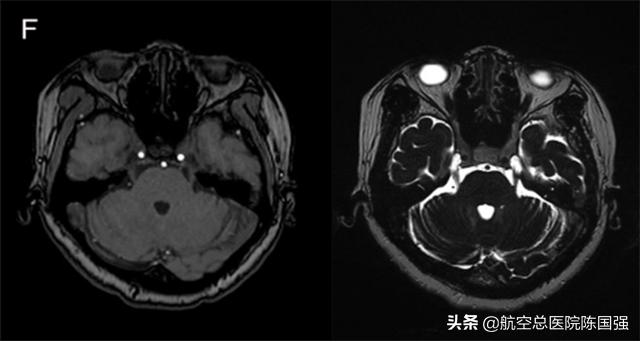

姜女士术前MRI未见血管压迫,术中选择性切断三叉神经运动根(M)